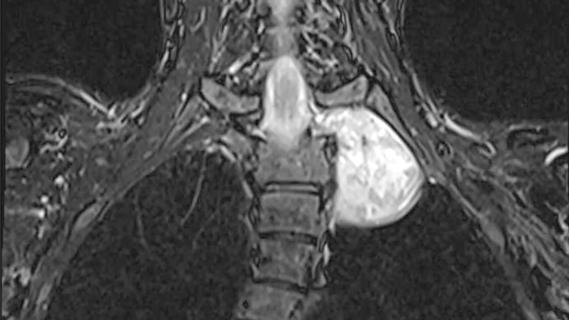

Nerve tumour in a patient's chest

Case Study: Removing a Tumour at the Intersection of the Spine, Lung and Major Arteries

Complex procedure highlights the power of coordinated care across spinal, thoracic and vascular surgery